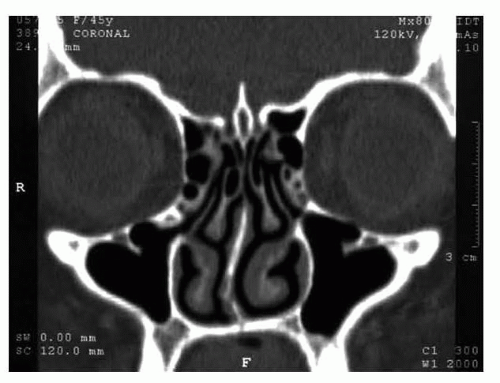

Computed tomographic (CT) imaging of the nose and perinasal sinuses is not obtained routinely but can provide valuable information in the following cases (FIG 1):

Patients with frequent sinus headaches, sinus infections, or migraine headaches

Patients for whom the extent of deviated structures are not clear after physical examination

Imaging provides clear visualization of the nasal bones, septum, turbinates, or a mass that may have contributed to the nasal deviation.

The CT may reveal many conditions such as septal deviation, large posterior spur sinusitis, concha bullosa, septal bullosa, Haller cell, and contact points.